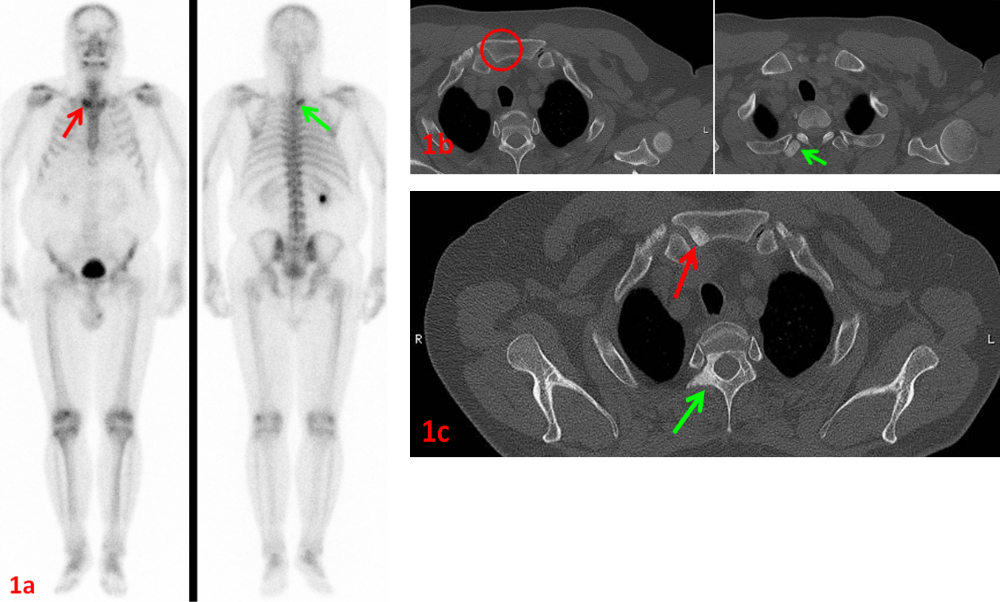

老年男性,右肺腺癌,ECT示胸骨柄右側(圖1a紅箭)、T2右側橫突(圖1a綠箭)代謝異常,考慮骨轉移。同期CT示胸骨柄未見異常(圖1b紅圈),T2右側橫突骨質密度略增高(圖1b綠箭)。

6個月后復查CT示胸骨柄(圖1c紅箭)、T2右側附件(圖1c綠箭)病灶骨質硬化,證實了ECT診斷的早期敏感性和準確性。